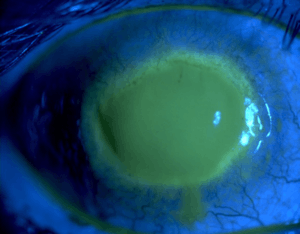

Acanthamoeba keratitis

Eye with Acanthamoeba keratitis (fluorescein observation) | |

Acanthamoeba keratitis is a rare disease in which amoebae invade the cornea of the eye. It may result in permanent visual impairment or blindness.[1][2]